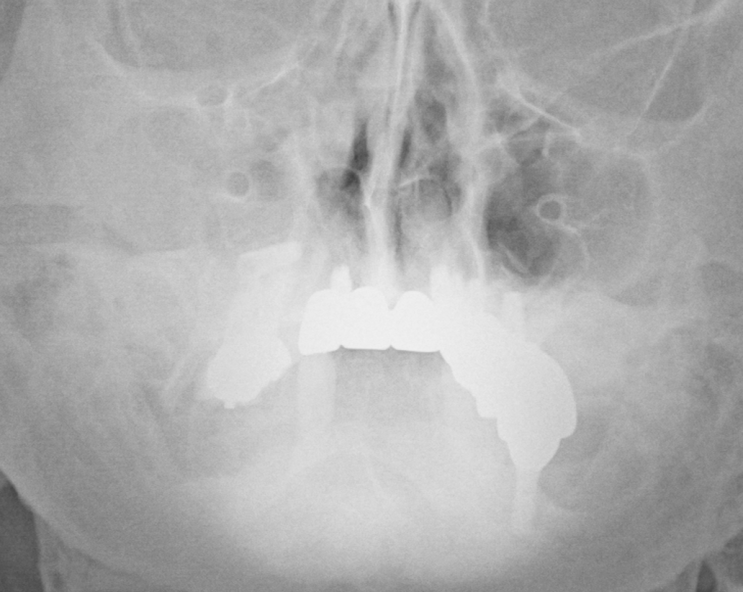

- 이물질에 의한 maxillary sinusitis 1예 지인분으로 수년전 부터 앓은 부비동염으로 집근처 ENT에서 ...